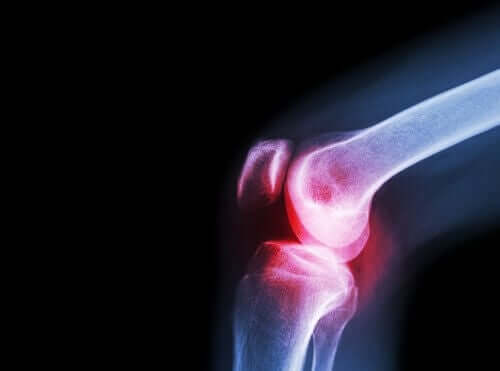

Lek ten przepisuje się w przypadkach, w których występują stany zapalne a także duża bolesność. Dlatego często używa się go do leczenia, takich dolegliwości jak ból krzyża, ból zęba i ból stawów.

Jest również wskazany w przewlekłym leczeniu bólu i stanów zapalnych związanych z przewlekłymi procesami chorobowymi stawów i kości. Chodzi miedzy innymi o zapalenie kości i stawów, reumatoidalne zapalenie stawów i zapalenie stawów kręgosłupa.

Reumatoidalne zapalenie stawów jest przewlekłą chorobą zapalną o charakterze autoimmunologicznym. Charakteryzuje się tym, że atakuje najczęściej wiele rożnych stawów a ponadto w chorobie tej rozwijają się również pewne ogólne i niespecyficzne objawy.

Jeśli chodzi o objawy, reumatoidalne zapalenie stawów zwykle objawia się bólem i sztywnością stawów. Często pojawiają się również trudności ruchowe w zakresie różnych małych i dużych stawów.

Wewnątrz stawów znajduje się płyn zwany mazią stawową wytwarzany przez błonę maziową. Końce kości, które łączą się w staw, są natomiast pokryte chrząstką stawową. Kiedy następuje uszkodzenie tej chrząstki, pojawia się ból, sztywność i upośledzenie czynnościowe.